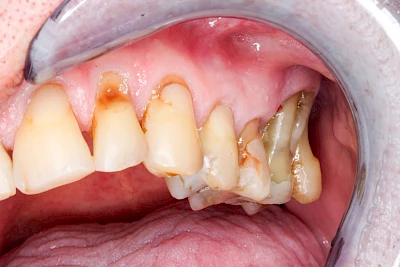

Gingivitis & Parodontitis: Stadien

Ist zunächst nur das Zahnfleisch von der Entzündung betroffen, spricht man von Gingivitis. Später, wenn auch der Knochen um die Zähne herum entzündet ist, spricht man von einer Parodontitis. Bei der Parodontitis wird der Knochen nach und nach abgebaut und das Zahnfleisch zieht sich zurück. Die Zahnhälse und Zahnwurzeloberflächen liegen mehr und mehr frei. Die Zähne werden zunehmend lockerer und fallen schließlich aus.

Bei Implantaten – also operativ eingebrachten künstlichen Zahnwurzeln – kann der Körper die Bakterien auch nicht so gut abwehren. Hier spricht man im Fall einer Entzündung von einer Peri-Implantitis, also einer Entzündung um das Implantat herum.